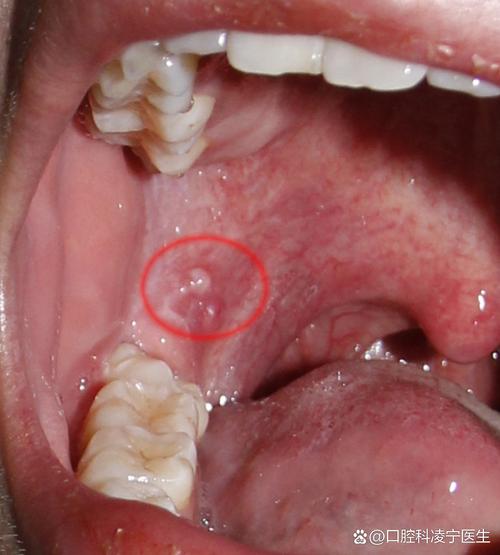

口腔有结节是什么症状 口腔内出现任何不明原因的、长期不消退的肿块或结节,都应立即咨询口腔科医生或口腔颌面外科医生进行专业诊断。 这是最关键的一步,因为原因可能多种多样,从良性的到恶性的都有。(图片来源网络,侵删) 下面我将为您详细解析口腔结节可能出现的症状、可能的原因以及您应该怎么做。 口腔结节可能伴随的症状 除了能摸到...

口腔内有白色的小疙瘩 仅为医学科普和参考,不能替代专业医生的诊断,口腔情况复杂,强烈建议您及时去看牙医或口腔黏膜科医生,以便得到准确的诊断和治疗方案。(图片来源网络,侵删) 以下是可能导致口腔内白色小疙瘩的一些常见原因,您可以对照参考,但最终请以医生诊断为准: 生理性或良性原因(通常无需过度担心) 皮脂腺异位(Fordy...